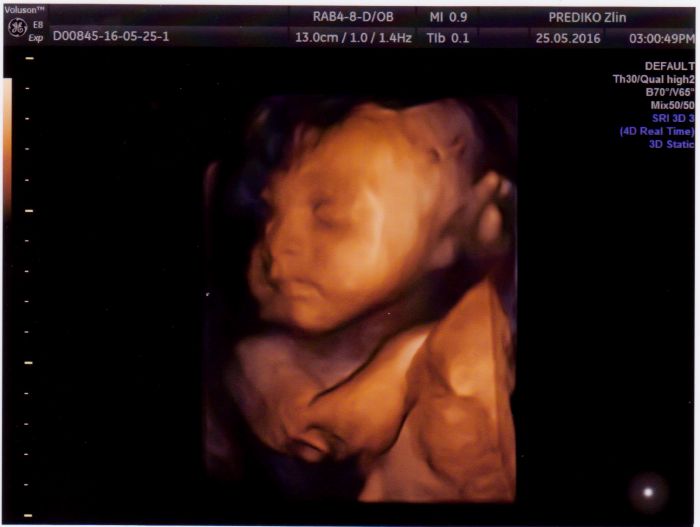

Ahoj holky, včera jsme byli na 3D ultrazvuku a mám krásné fotky, tak se musím pochlubit. Dnes jsem 28+2 a mám nahoře 11 kg. V prvním těhu jsem přibrala celkem 20kg, ale 15 jsem nechala v porodnici. Tak snad to půjde dolů podobně. Divím se, že jsem s mým jídelníčkem nepřibrala víc, ale je pravda, že furt běhám za malou nebo někde trajdáme venku.

Míšo na té první fotce je to pěknej puclík :-)